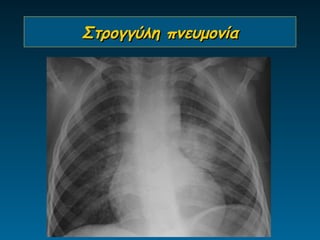

Στρογγύλη πνευμονία